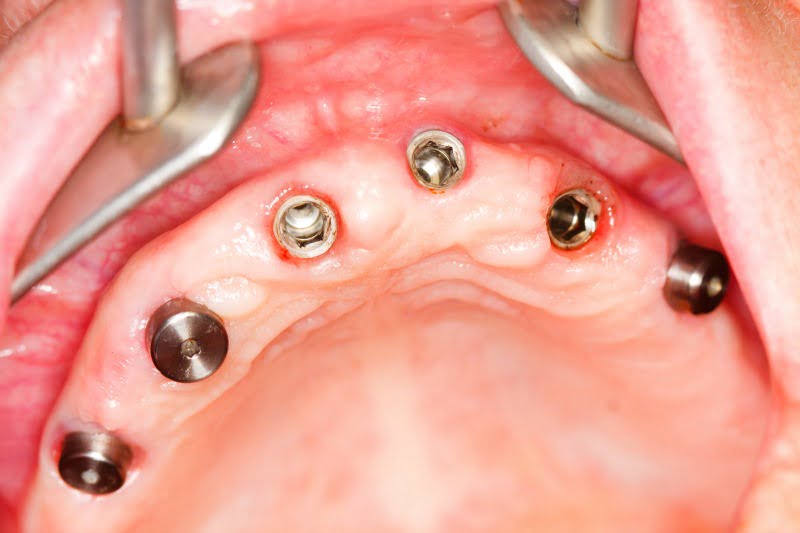

No estudo, a taxa de insucesso nos implantes era três vezes superior em pacientes com bruxismo do que em pacientes que não sofrem desta perturbação. Com vista a esclarecer a associação entre bruxismo e o risco de insucesso em implantologia, os investigadores analisaram dados relativos a 3 549 implantes, colocados em 994 pacientes.

Neste grupo, 56 pacientes (com 185 implantes no total) sofriam de bruxismo. No total registou-se insucesso em 179 implantes. Ao comparar a taxa de insucesso entre pacientes com bruxismo e pacientes sem a patologia, os investigadores suecos descobriram que as taxas de insucesso eram treze e 4,6 por cento, respetivamente. Assim, o risco de perder um implante era quase três vezes superior no grupo com bruxismo, indicou o atual estudo.